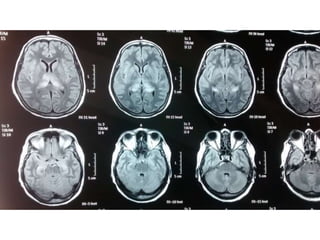

MRI of brain-JE